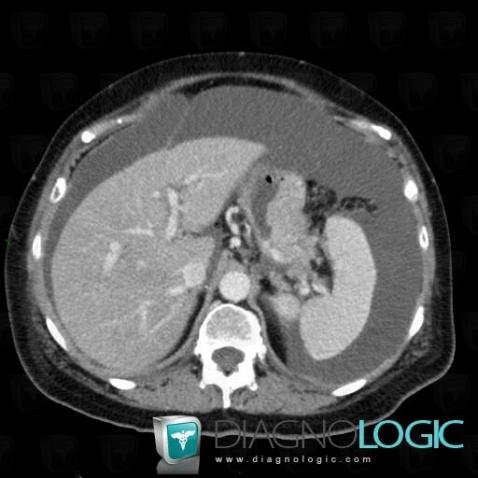

Cancer gastrique, Estomac, Scanner

Voici les informations spécifiques à l'image clé ci dessus:

- Diagnostic Cancer gastrique, Localisation(s) Estomac, comportant les gammes Masse ou lacune gastrique